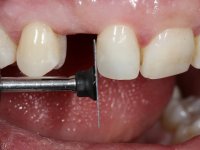

To define the dental zone to be covered by the Maryland bridge retainers, the patient was asked to perform maximum intercuspidation movements, and the contact points were marked with articular paper. Tooth preparation of the interproximal surfaces was made, to create a prosthetic insertion axis. It was sought that the mesio-distal diameter at the incisal level was equal to the diameter mesio-distal at the cervical level, that is to say, the interproximal walls were parallelized. Tooth preparation was done with fine grain diamond drills, and later polishing was done with abrasive discs. Color information was collected even before confection of the impression, to avoid dehydration of the arcade. Definitive impression was made using wash technique impression with silicone of heavy and regular consistency, both with fast setting, and a working plaster model was prepared in the lab. A laboratory scanner was used to scan the working model, and later, the infrastructure for the Maryland bridge was made using a CAD-CAM process. Ceramic was placed on this subframe. A ceramic adhesive was applied to the internal surface of the wings and connectors, which would enable bonding to the adjacent teeth. The adhesive bridge was bonded in the mouth following the conventional bonding technique. After bonding, the protrusion and laterality movements were carefully checked to avoid undesirable contacts.